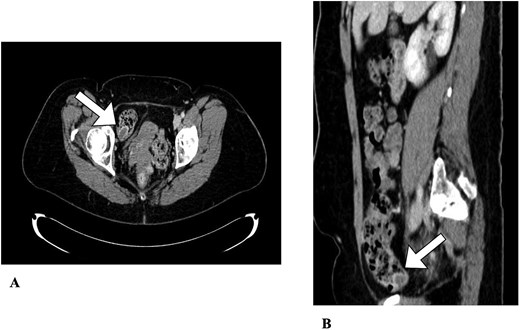

A 52-year-old female was found to have an invaginated appendix on routine screening colonoscopy (Fig. 1). She underwent subsequent computed tomography (CT) which confirmed the appendix inverting into the cecum (Fig. 2). The patient presented with no acute appendicitis or abdominal symptoms. Due to the inability to rule out appendiceal neoplasm, she was provided treatment options including surveillance and surgical removal. The patient elected to have a robotic assisted appendectomy with possible ileocecal resection depending on severity of disease. Her medical history was significant for prior cesarean section, which was evident during the robotic procedure as the uterus was adhered to the lower abdominal wall. There was no visible appendix in the right iliac fossa during inspection, but tissue could be palpated within the distal cecum. During the procedure, it was determined that the ileocecal resection was not necessary. Instead, a partial cecectomy with appendectomy was performed to spare the ileocecal valve as it was not involved. Resected margins were 3.5 × 2.7 × 0.3 cm with the inverted appendix measuring 1.8 × 1.0 cm. The operation was performed without complications, and the patient was able to be discharged later that day. The postoperative period was without complications.

Abdominal CT. An appendiceal cecal intussusception is present (arrows) with the distally located appendix invaginating into the proximally located cecum. (A) Axial view. (B) Sagittal view.